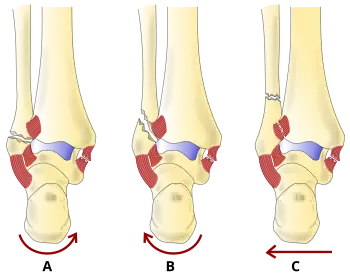

Danis–Weber classification of ankle fractures (Types A, B and C)

The Danis–Weber classification (often known just as the Weber classification) is a method of describing ankle fractures. It has three categories:[1]

Type A

Fracture of the fibula distal to the syndesmosis (the connection between the distal ends of the tibia and fibula). Typical features:

• below level of the ankle joint

• tibiofibular syndesmosis intact

• deltoid ligament intact

• medial malleolus occasionally fractured

• usually stable: occasionally nonetheless requires an open reduction and internal fixation (ORIF) particularly if medial malleolus fractured

Type B

Fracture of the fibula at the level of the syndesmosis. Typical features:

• at the level of the ankle joint, extending superiorly and laterally up the fibula

• tibiofibular syndesmosis intact or only partially torn, but no widening of the distal tibiofibular articulation

• medial malleolus may be fractured or deltoid ligament may be torn

• variable stability

Type C

Fracture of the fibula proximal to the syndesmosis. Typical features:

• above the level of the ankle joint

• tibiofibular syndesmosis disrupted with widening of the distal tibiofibular articulation

• medial malleolus fracture or deltoid ligament injury present

• unstable: requires ORIF

Categories B and C imply a degree of damage to the syndesmosis itself (which cannot be directly visualised on X-ray). They are inherently unstable and are more likely to require operative repair to achieve a good outcome. Type A fractures are usually stable and can be managed with simple measures, such as a plaster of paris cast.